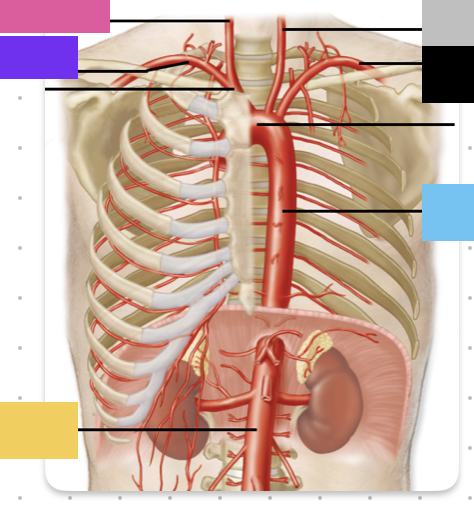

purple

left pulmonary artery

black

left pulmonary veins

blue

(branches of) right pulmonary artery

yellow

right pulmonary veins

orange

ascending aorta

purple

aortic arch

yellow

brachiocephalic trunk (blue)

pink

right common carotid artery

purple

right subclavian artery

red

left common carotid artery (grey)

green

left subclavian artery (black)

blue

descending aorta

blue

thoracic aorta

yellow

abdominal aorta